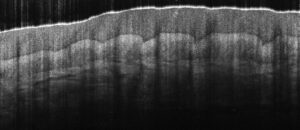

Better roll-off performance and greater camera sensitivity enables visualization of deep vasculature in the dermis.